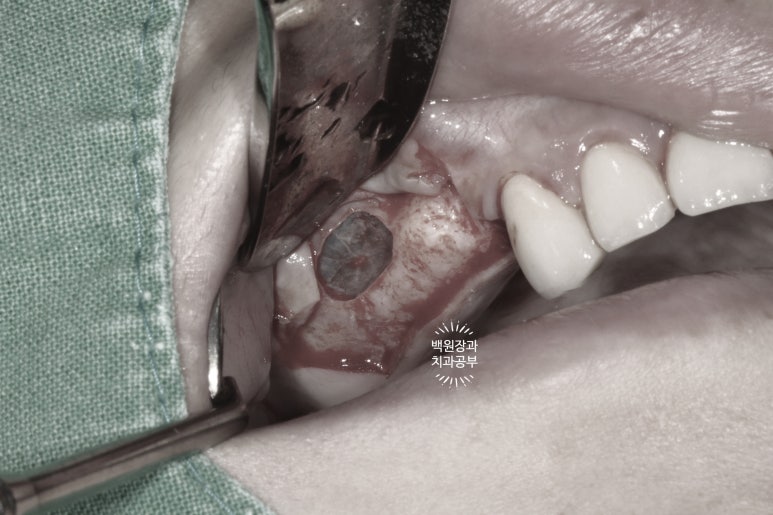

머릿속에 계획했던 도식대로 측방접근법을 이용하여 lateral 부위에 window를 형성해 줍니다.

이를 위해 아까 언급했던 초음파 골삭제 기구가 참으로 많은 도움이 됩니다.

이 기계 한개에 천만원이랍니다.... 그치만 마치 게임처럼.. 수술도 장비빨 무시 못합니다.

좋은 결과를 위해서 투자가 필요한 대목. ㅎㅎ

연세대학교 치과대학병원 치주과에서부터 사용하던 기계입니다.

아까 보시던 얇은 상악동막을 기존의 치조골에서 박리 후, 원하는 만큼 뼈이식을 해둡니다.